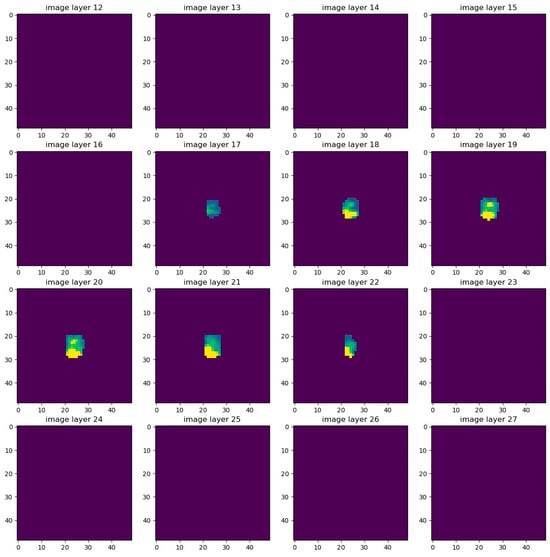

The first approach was to mask the previously mentioned structures UB, colon and hip bones. An overview of this masking can be seen in the following Figure A4. Here, 16 image layers of the PET channel around the prostate in one patient were visualized together with the mask.

Figure A4. 16 layers of an image with visible PET channel and masking of UB, colon and hip bones.

Cancers 17 01575 g0a4

Overview of 16 image layers of the PET channel around the prostate of a patient. Between layer 18 and layer 23, the prostate can be seen as a yellow-green signal. The mask is also clearly visible, as it can be recognized as completely dark areas. The ventral side of the patient is on the right side of the images, while the dorsal side is on the left side of the images. The patient’s right hip bone is on the upper side of the images, while the patient’s left hip bone is on the lower side.